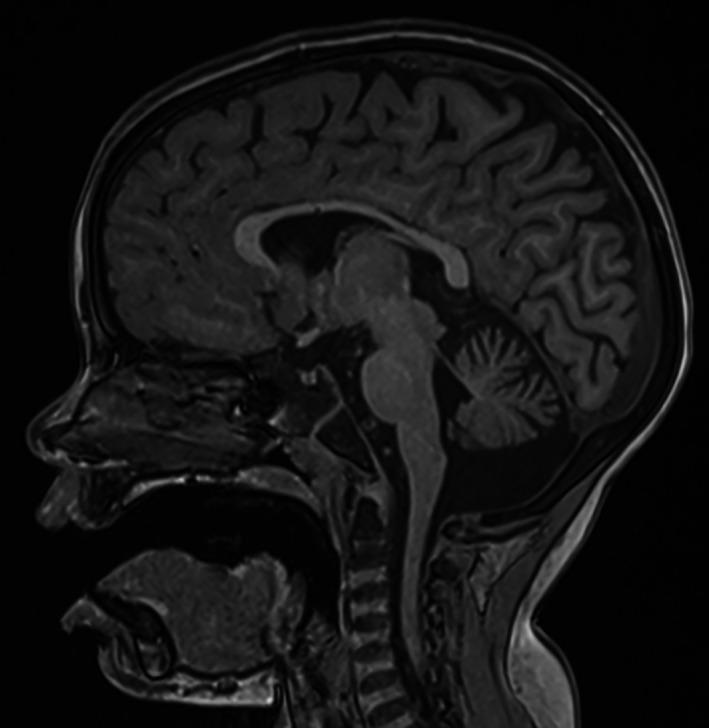

A Hispanic woman with unremarkable medical history experienced progressive lower-limb spasticity in her 20s and received a diagnosis of HSP. She developed significant gait abnormalities and is unable to walk without assistance. More recently, two Hispanic brothers with childhood-onset manifestations including lower-limb spasticity, developmental delays, and seizures presented with suspected HSP. All three patients were ultimately diagnosed with ARG1-D based on plasma arginine several-fold above normal levels and loss-of-function variants. Disease progression occurred before ARG1-D was correctly diagnosed.

一名无明显病史的西班牙裔女性在20多岁时出现进行性下肢痉挛,并被诊断为HSP。她出现了明显的步态异常,没有帮助无法行走。最近,两名患有儿童期发病症状(包括下肢痉挛、发育迟缓及癫痫发作)的西班牙裔兄弟疑似患有HSP。基于血浆精氨酸水平高于正常水平数倍及功能缺失变异,所有三名患者最终被诊断为ARG1-D。在ARG1-D被正确诊断之前疾病已经进展。